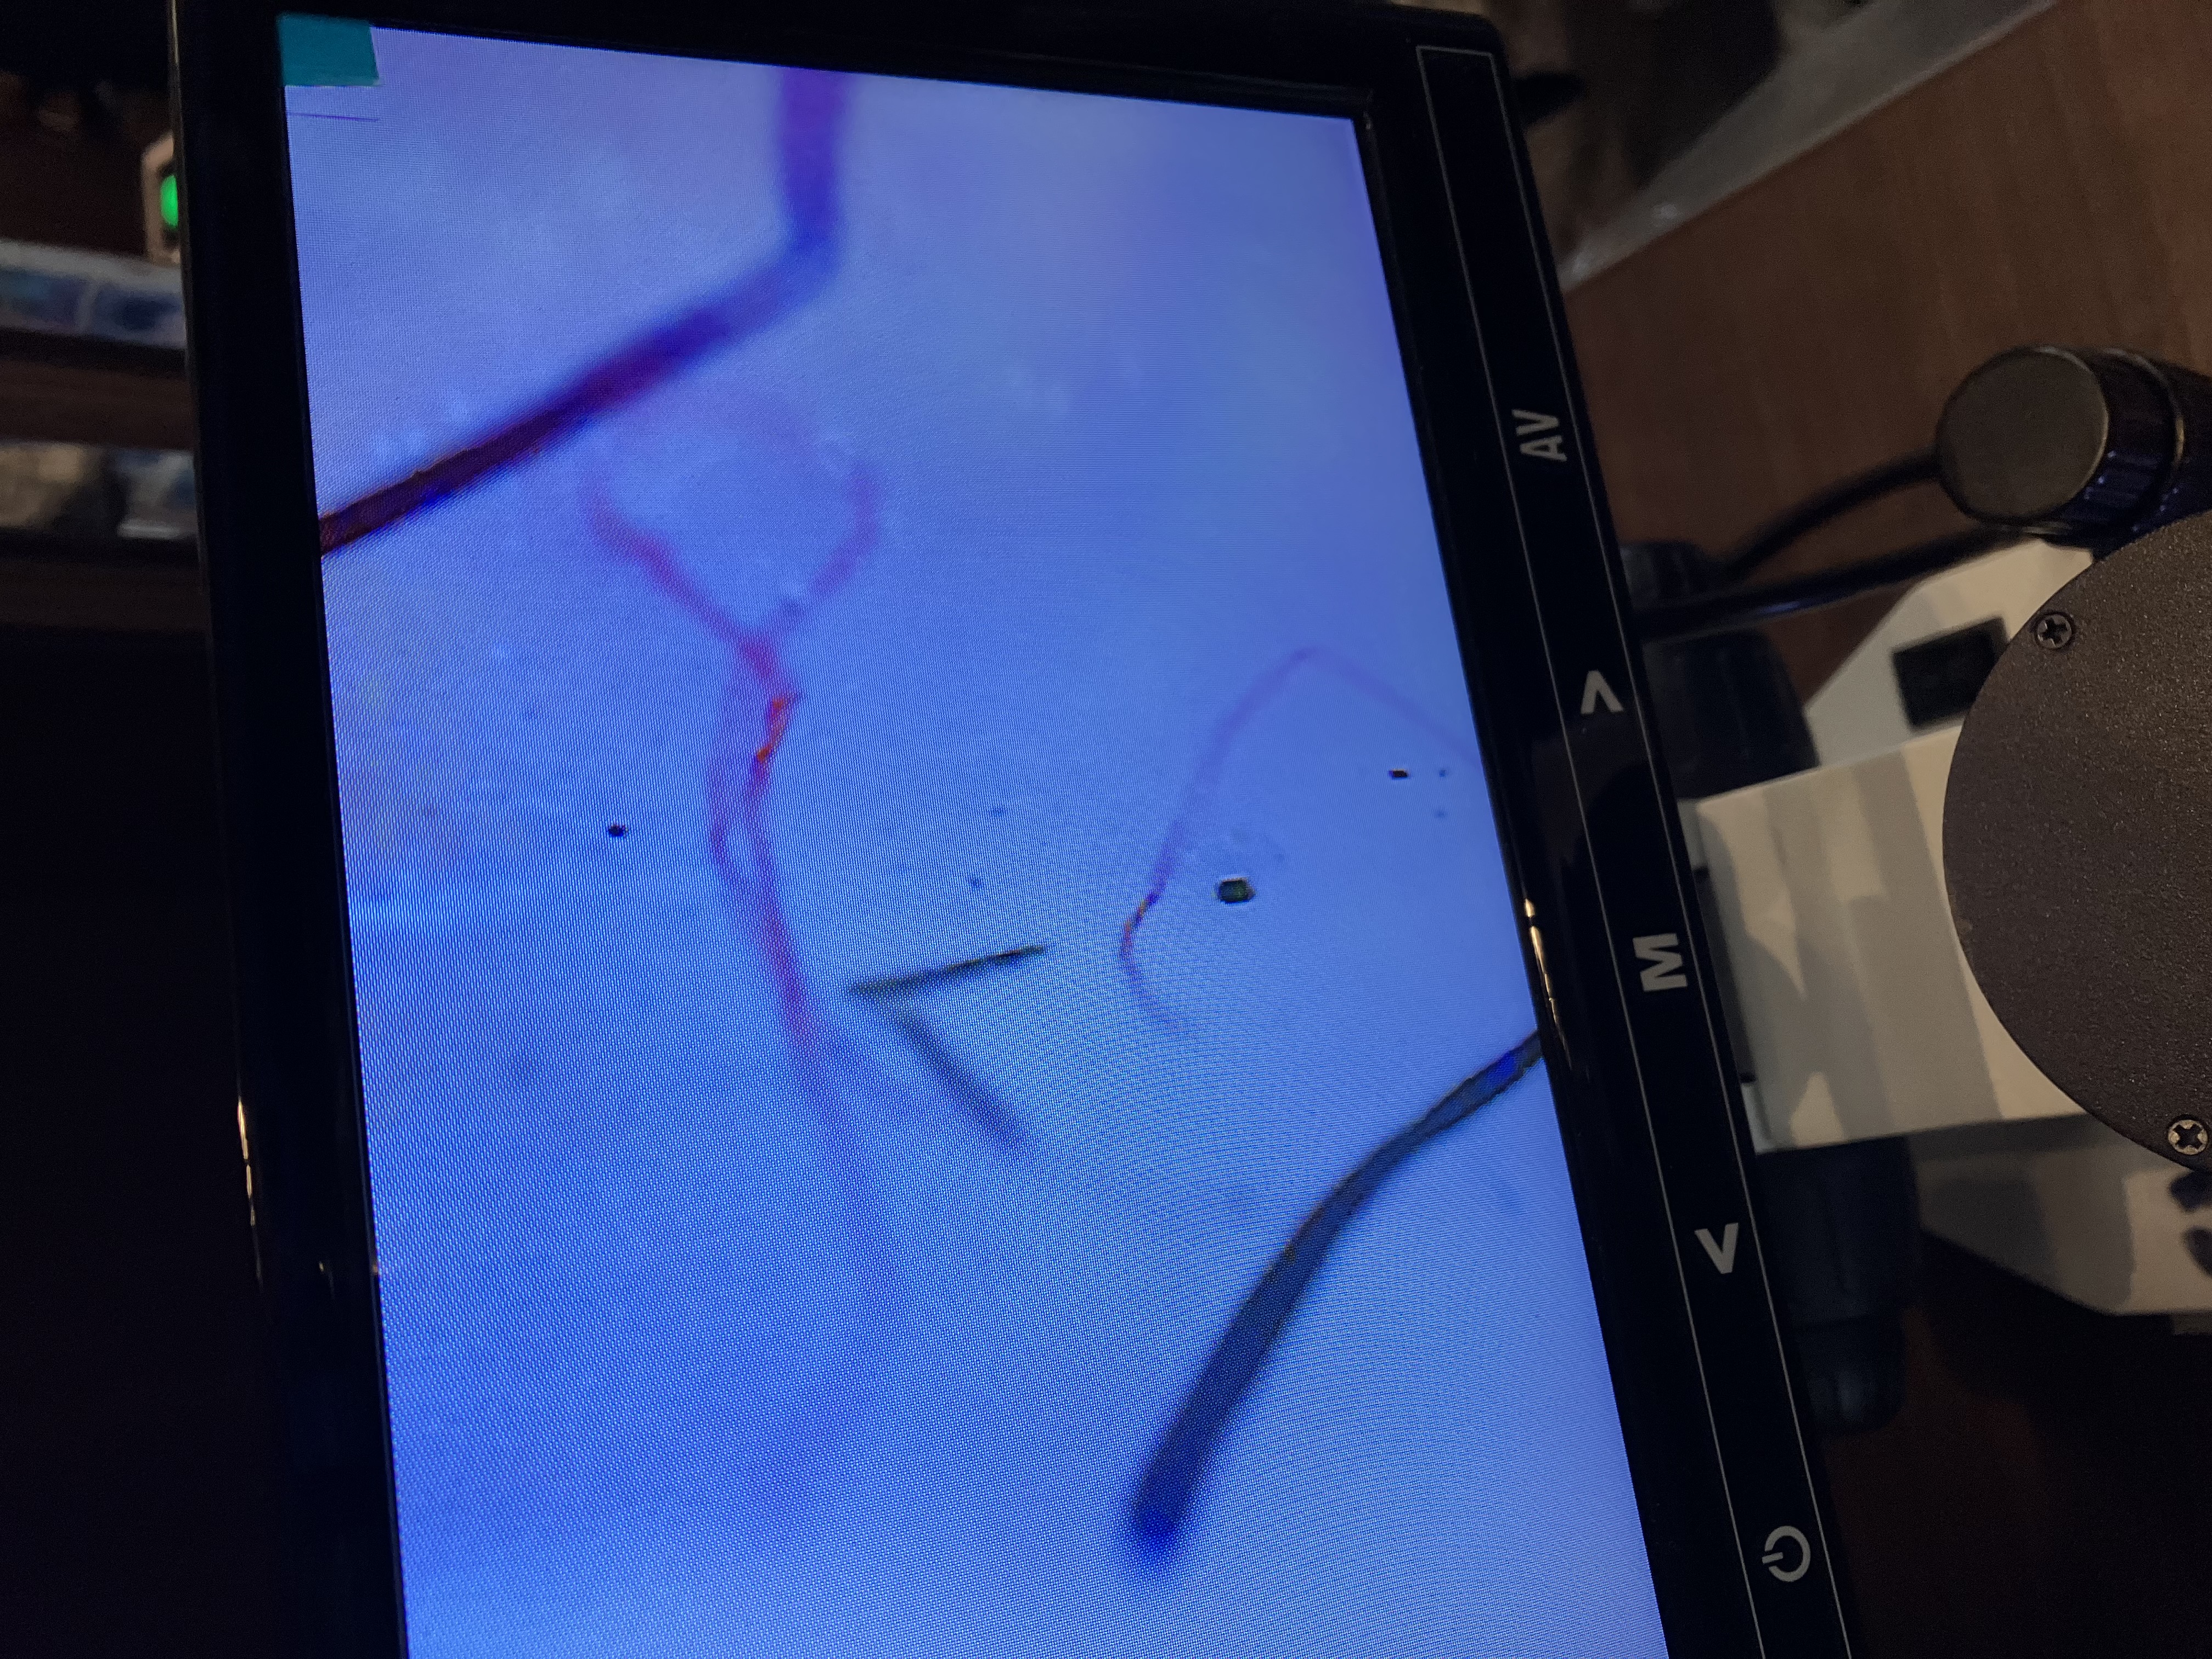

独自の技術で不調からの解放へ。今こそ元気を取り戻そう。